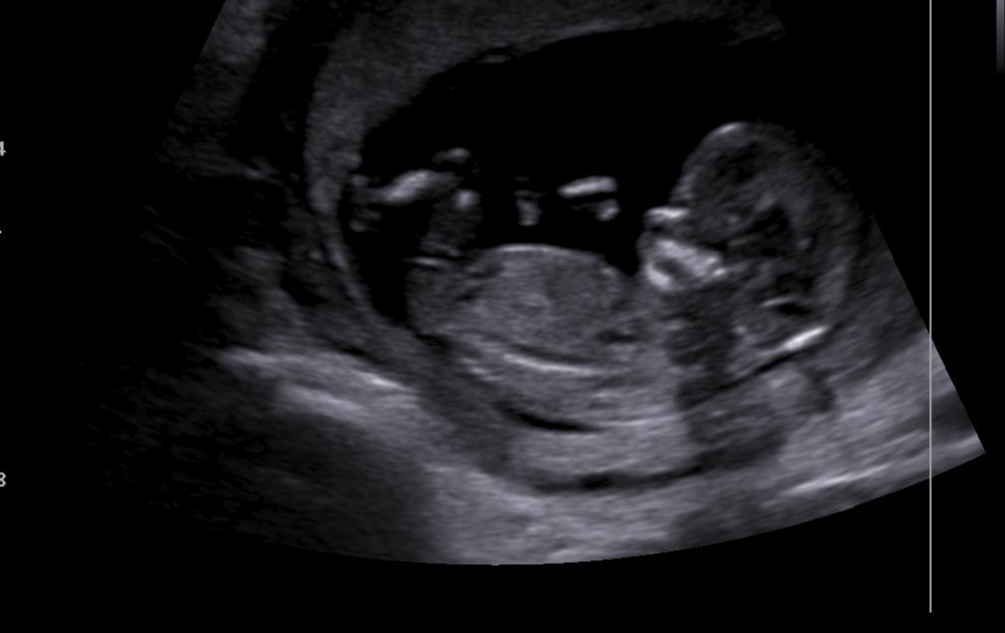

Holčička nebo chlapeček? Jde to poznat?

@hanussenka Podle téhle fotky bych se klonila spis k holčičce, ale fotky často zkresluji... Je třeba sledovat ultrazvuk, jestli tam hrbolek směřuje nahoru (chlapeček), nebo jde rovnoběžně s páteří (většinou takové 2 čárky)=holcicka 🙂. Já jsem takhle syna ve 13.tt poznala a teď si myslím, ze to bude holka :D, ale potvrdí mi to v úterý, tak jsem zvedava, jestli jsem to zase uhodla... Jinak jak který dr... Někteří to říkat nechtějí, protože v některých případech se to urcit nedá, nebo je to sporné, ale pokud je zkušený, tak bud ví, nebo řekne, ze je to zkratka v “šedé zóně” a musíte počkat 🙂.

@andreajkab Je sice brzy, ale pri správném natočení a dobre fotecce se dá odhadnout, co se z toho vyvrbi. Zkušený lékař to dokáže urcit dokonce s téměř 90%jistotou. Ovšem tahle fotka je dost rozmazana a pohlavní hrbolek zakrývá nozicka :(...Takže asi nikdo neporadí... Neco jako hrbolek tam trcí, takže bych tipla holcicku, ale neni vidět cely a nejsem žádný odborník, takže to skutečně berte jen jako tip ;)